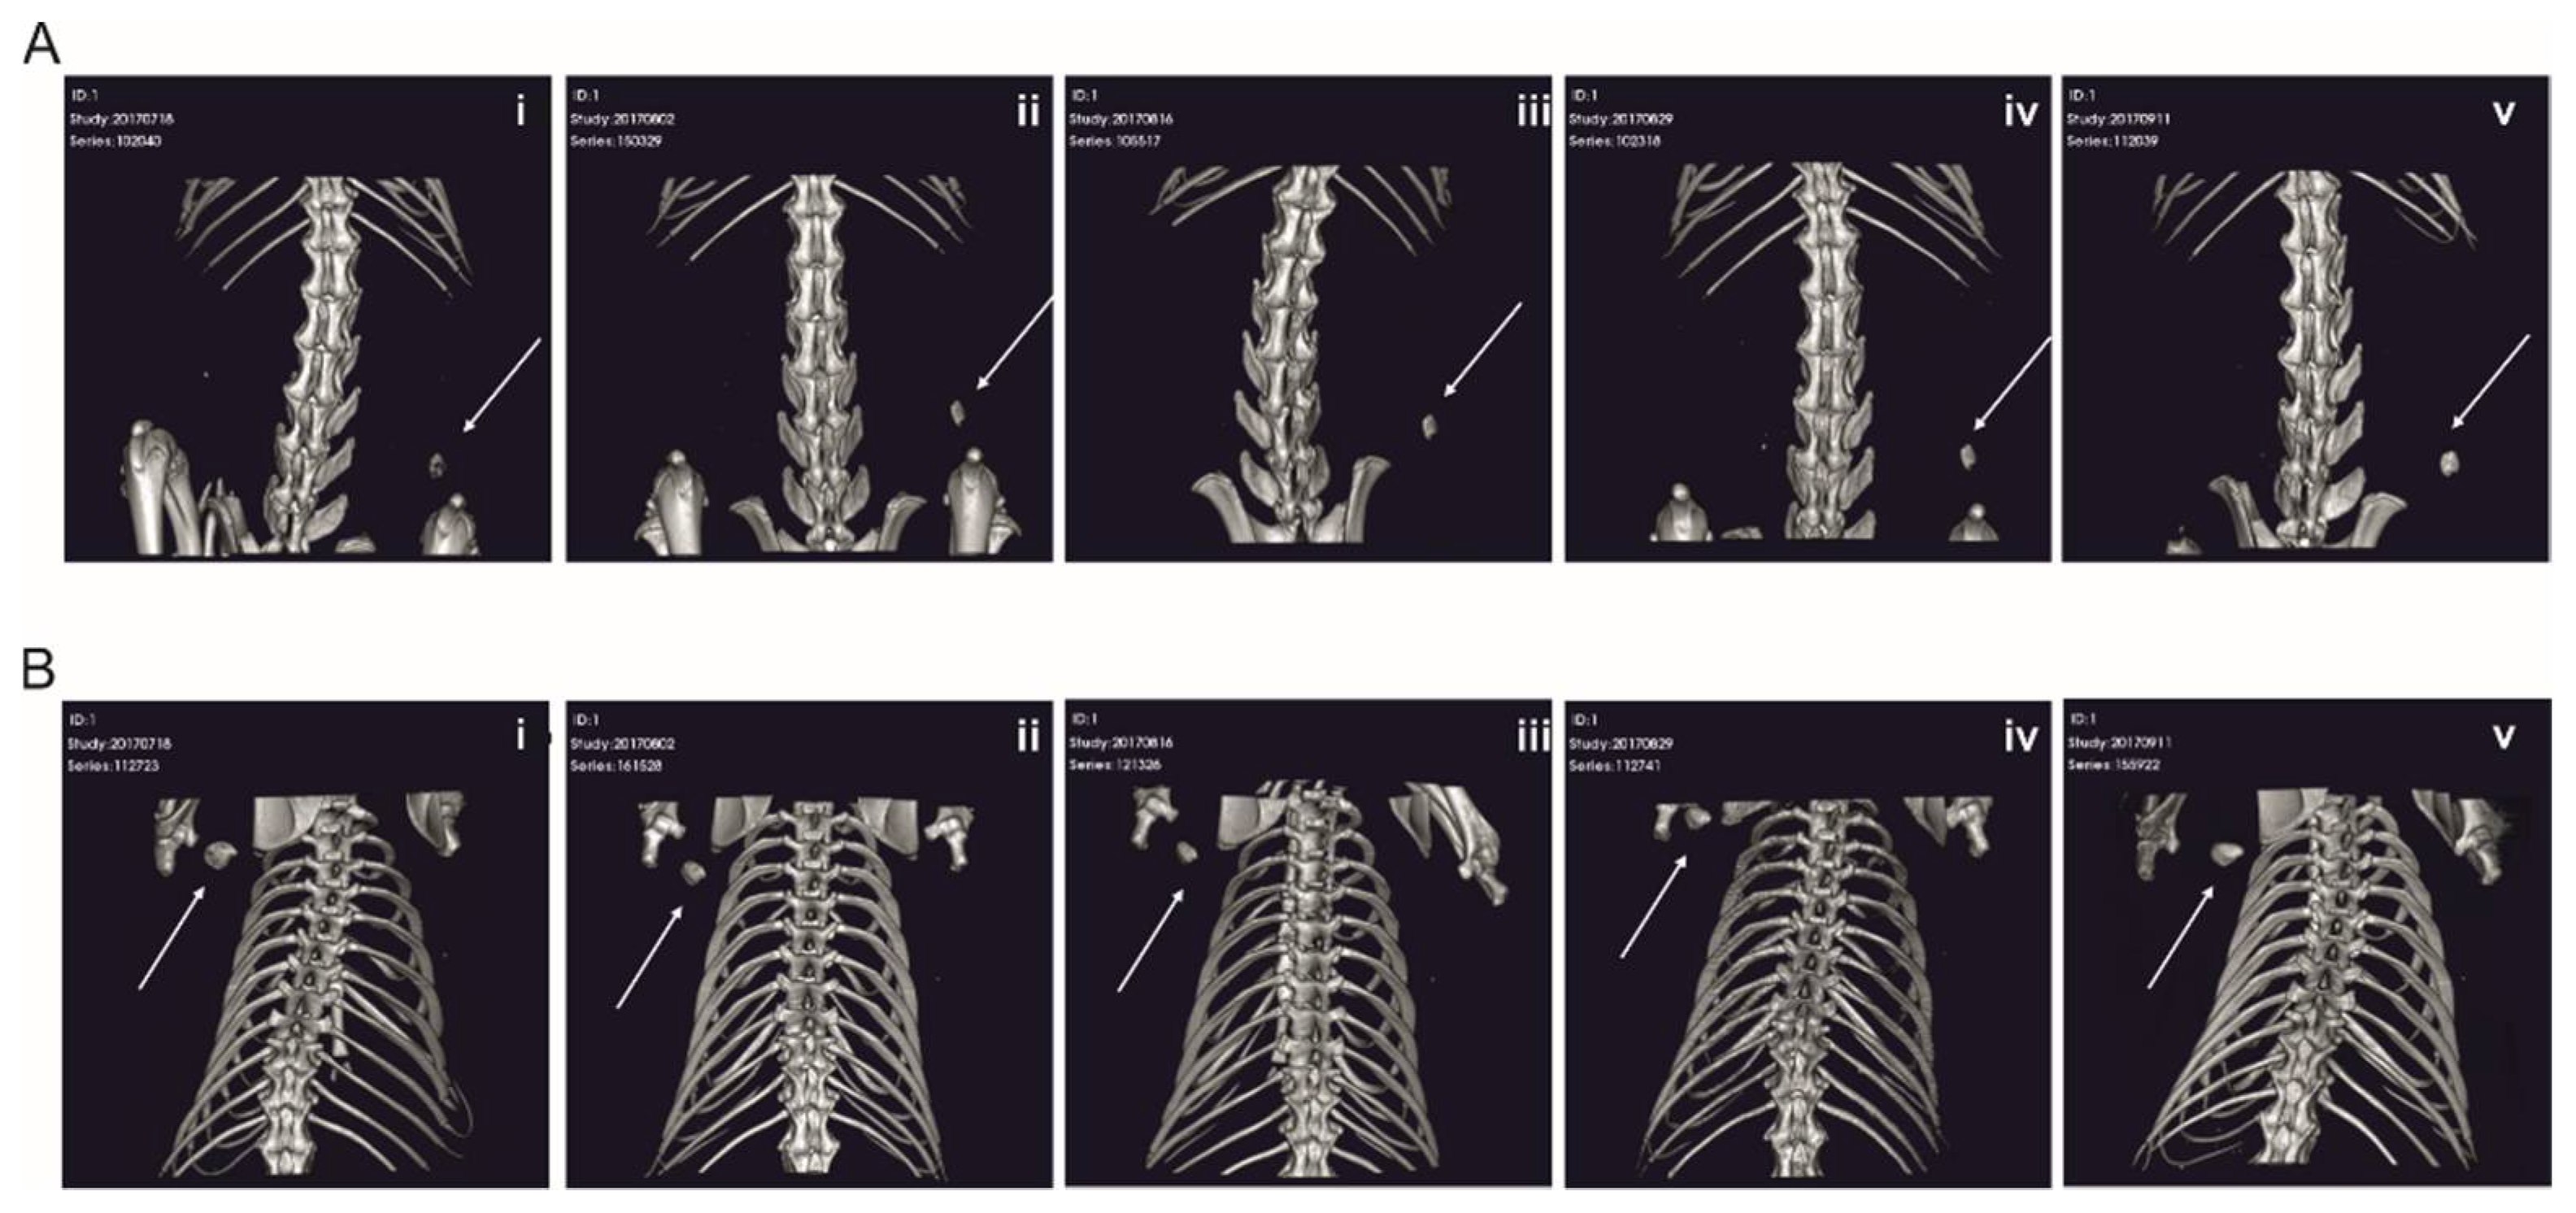

2.4. RCP Microspheres Functionalized with the Covalently Coupled BMP2 Azide Induce Ectopic Bone Formation with Similar Bone Volume and Density as Ad/Absorbed BMP2 WT

2.5. The Morphology of the De-Novo-Induced Bone Tissue Highly Varies Depending on the Specific Immobilization Technique

3.3. The Delivery Methods Significantly Affect the Morphology of the Ectopically Formed Bone